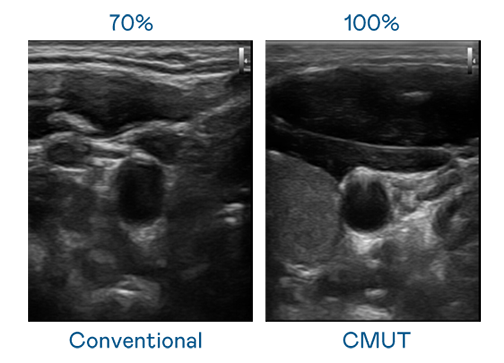

CMUT 技术是一种用电容式微机电元件来产生超音波讯号的技术。与传统 PZT 压电式技术相比,CMUT 频宽增加 30%,更宽频的超音波讯号让影像解析度大幅提升,是实现高影像品质医疗超音波扫描、促进精准医疗发展的关键技术。

超音波影像的解析度高低,首先取决于探头能发出的讯号频宽。MK体育 CMUT 可提供高清晰的超音波讯号,提供高频宽、高灵敏度、影像纹理细节更高的超音波影像,协助医护人员缩短影像判读时间及利用精准的医疗影像进行诊断。